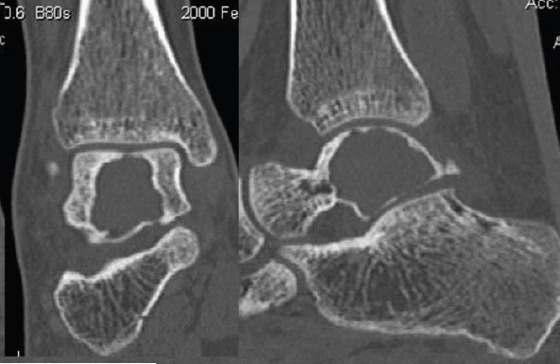

Case report: We report a case of this rare lesion managed in our department. It was a 16-year-old girl who presented with heel pain at walk, without any trauma. Radiologic explorations found a pathologic fracture of the right talus due to a bone cyst. A surgical procedure was proceeded, with curettage, and bone grafting completed by a plastered immobilization. Histopathology confirmed the diagnosis of ABC. Consolidation was achieved in 2 months, and there was no recurrence after 5 years.